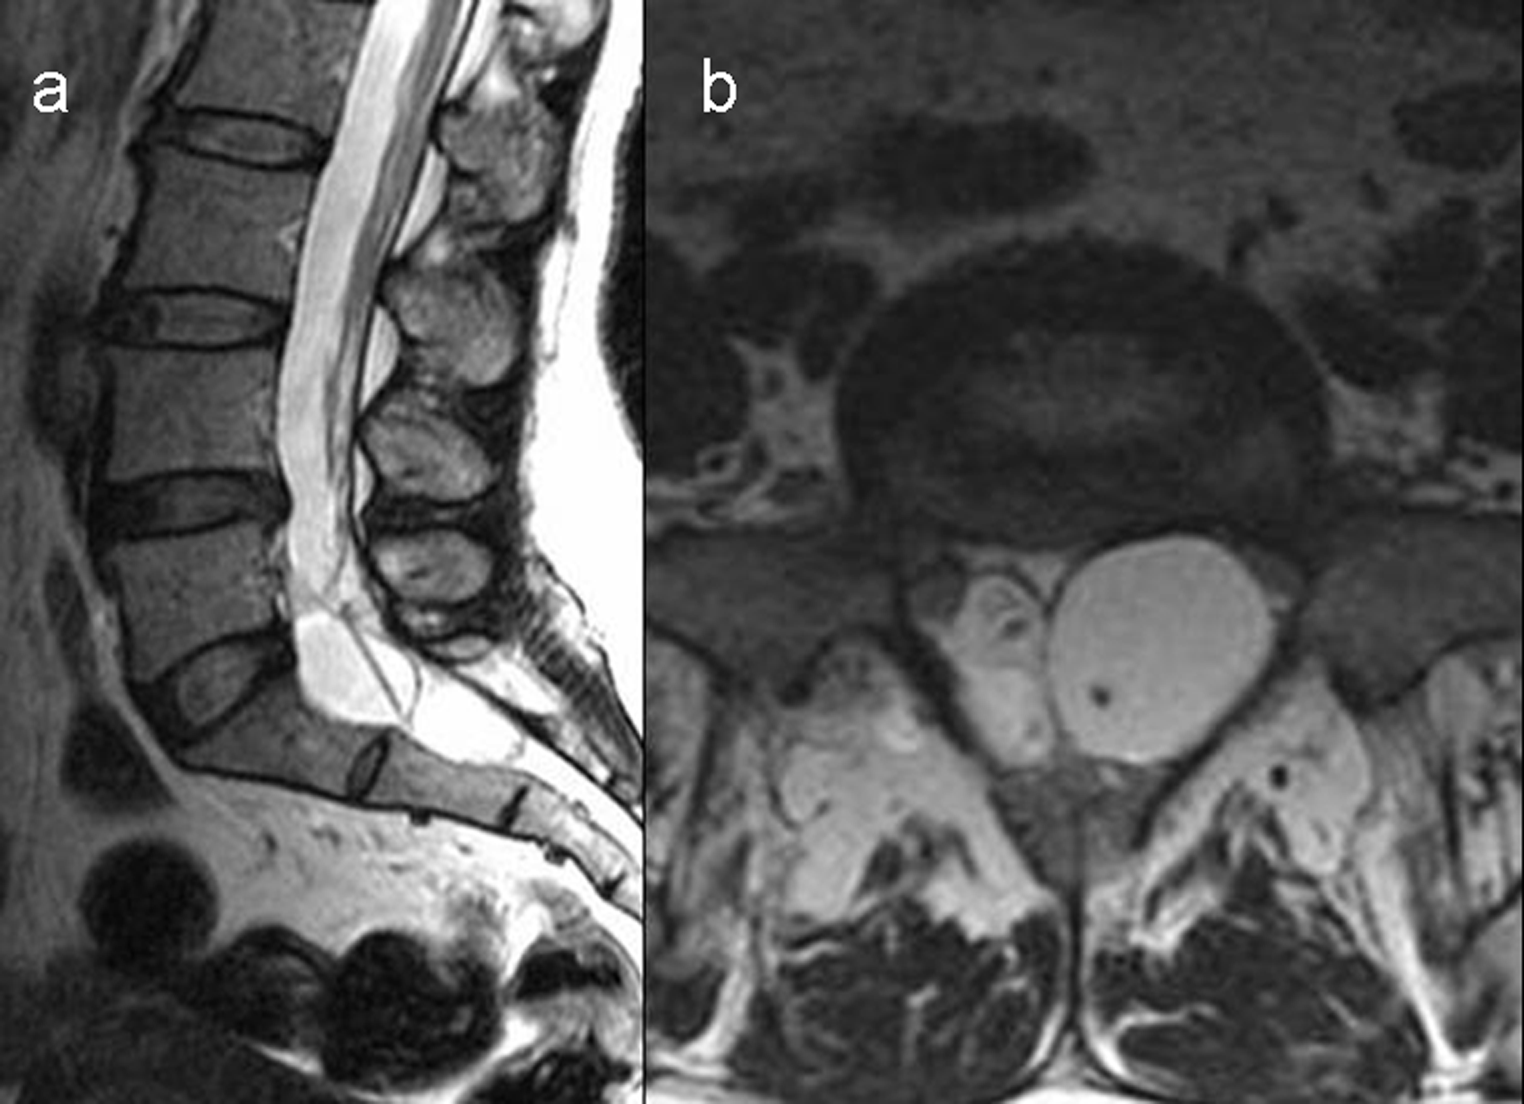

Results: All cystic lesions showed hypointense signal intensity on T1WI and hyperintense signal intensity on T2WI, but the nerve root showed iso-intensity on T1WI and low signal intensity on T2WI. They were linear in shape on sagittal view, and hypo intense dotted spots within the cysts on traverse view. Surrounding structures of the larger cysts were compressed and had bone erosions in some cases; the spinal canal and the intervertebral foramen on the affected side were enlarged. The lesions/cyst wall showed no enhancement after gadolinium administration.